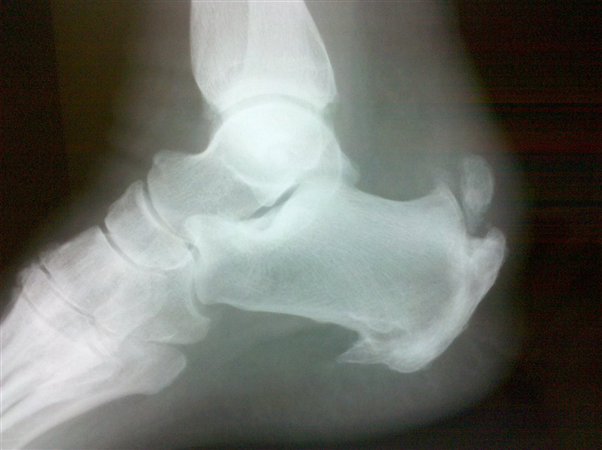

• lateral foot shows bone spur and intratendinous calcification

• lateral of foot demonstrates Haglund deformity